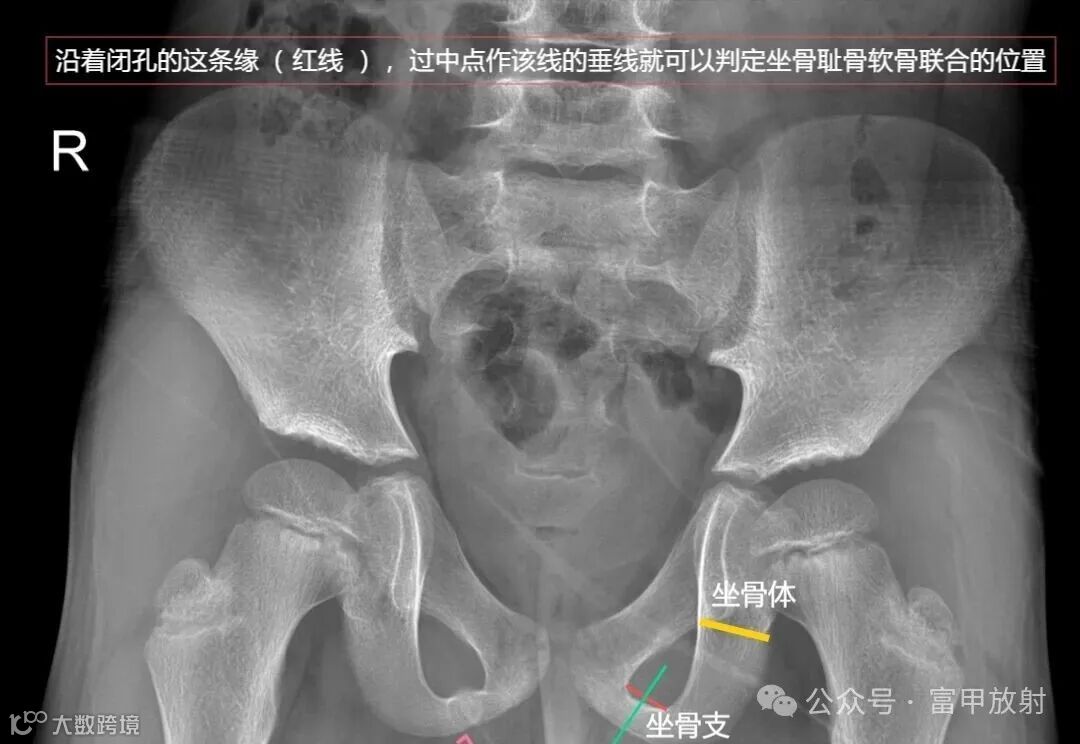

耻骨下支与坐骨分界在哪里?

坐骨结节是坐骨支的突起,是腘绳肌等附着的地方,耻骨结节是耻骨上支内侧缘的突起,腹股沟韧带附着点,在X线上坐骨结节也许估计到,耻骨结节基本上找不到,在这基础上作测量定位置,可靠性会不理想。以下这个简单的方法也许可以帮助到你。